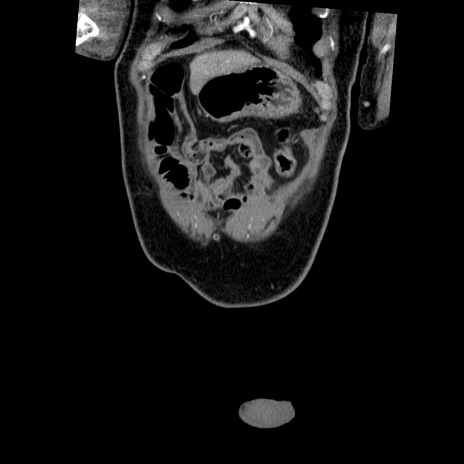

症例22(冠状断像)

【症例】50歳代男性

【主訴】腹痛

【現病歴】AVMからの被殻出血のため回復期リハ病棟入院中。 本日午後3時頃急に下腹部痛が出現した。

【既往歴】AVM、被殻出血、虫垂炎、高血圧

【身体所見】意識晴明、左半身不全麻痺、会話の理解は良好、36.5°C、腹部:膨隆、全体に板状硬、下腹部正中に圧痛点あり、反跳痛-、筋性防御不明、右下腹部にope scar

【データ】WBC 9400、CRP 0.06

横断像